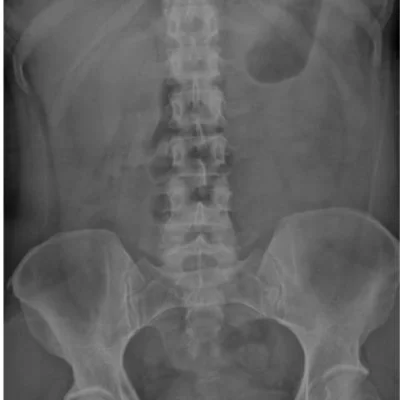

Abdomen X-Ray

Useful for detecting bowel obstruction, kidney stones, or abnormal gas patterns.